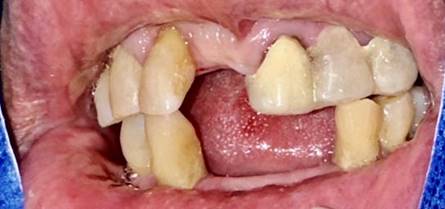

Paciente de sexo masculino, de 80 años, acude a la consulta refiriendo problemas en la masticación a causa de la pérdida avanzada dental, durante la apertura de la historia clínica en la anamnesis no refirió antecedentes patológicos personales, mientras que en los antecedentes patológicos familiares informo que sus padres tenían hipertensión arterial; además refirió antecedentes de enfermedad periodontal y un tratamiento previo hace 8 meses. En el examen extraoral no muestra patología aparente, mientras que en el examen intraoral presenta encías inflamadas, sangrado espontáneo, retracción gingival, acumulación de cálculo, bolsas periodontales de 6 mm, movilidad de las piezas dentales 4.3 y 4.4 del cuadrante inferior derecho con movilidad grado 3, y en el cuadrante superior derecho las piezas dentales 1.2 y 1.7 con movilidad grado 2 (Figura 1).

Figura 1. Fotografía intraoral de las arcadas superior e inferior. Se observan espacios edéntulos y puente provisional de acrílico.

Elaboración: Los autores.

Se aprecia la presencia de espacios desdentados en la arcada superior derecha de las piezas 1.1, 1.6, en el cuadrante superior izquierdo las piezas 2.2, 2.4, 2.5, 2.6, 2.7, en cuanto al cuadrante inferior derecho están ausentes las piezas 4.1, 4.2, 4.5, 4.6, 4.7, mientras que en el cuadrante inferior izquierdo las piezas ausentes son 3.1, 3.2, 3.6, 3.7, motivo por el cual presenta piezas extruidas por falta de contacto oclusal.